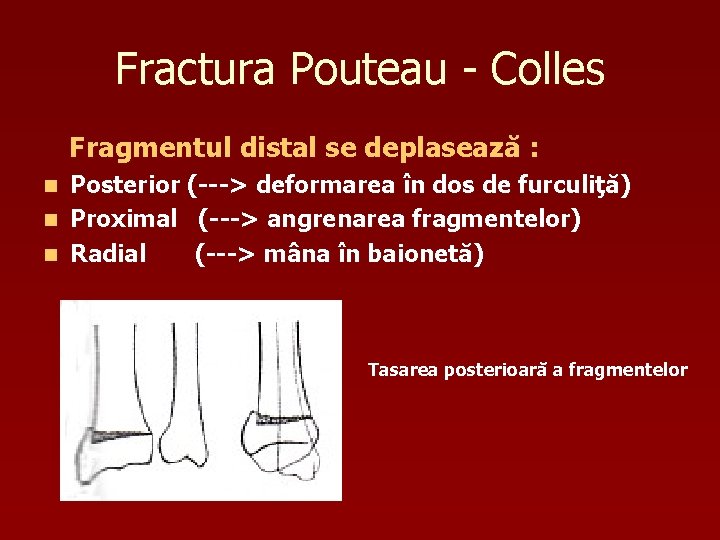

Fractura Pouteau - Colles Fragmentul distal se deplasează : Posterior (---> deformarea în dos de furculiţă) n Proximal (---> angrenarea fragmentelor) n Radial (---> mâna în baionetă) n Tasarea posterioară a fragmentelor